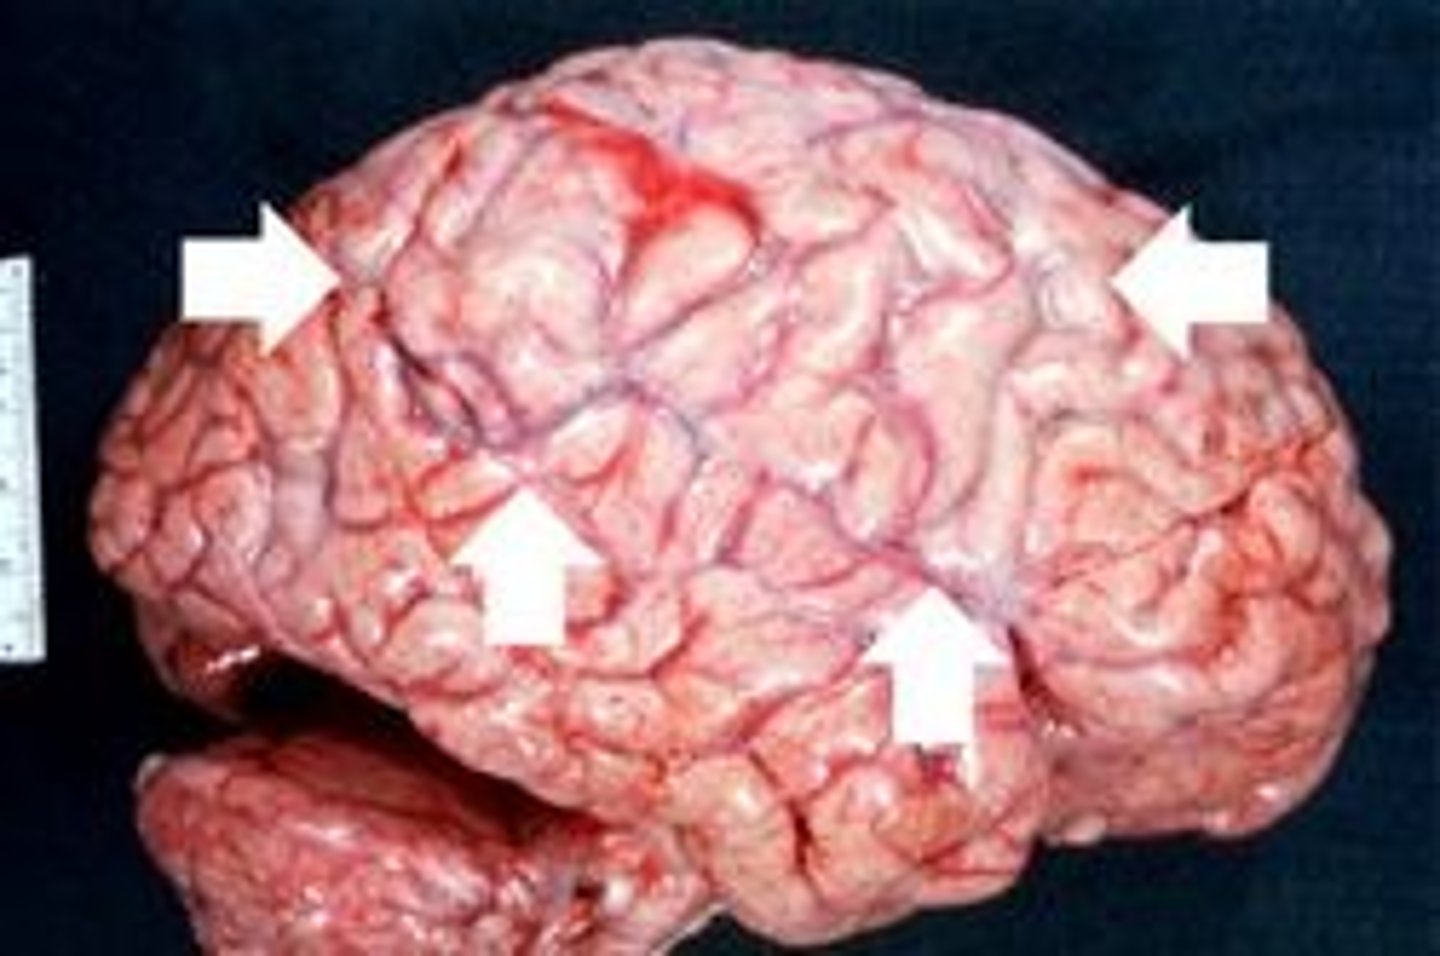

Bacterial (purulent) Meningitis

Pathogen: Haemophilus influenzae, Neisseria meningitidis, Streptococcus pneumoniae

S+S: Fever, headache, nuchal rigidity

Transmission: Respiratory or oropharyngeal secretions